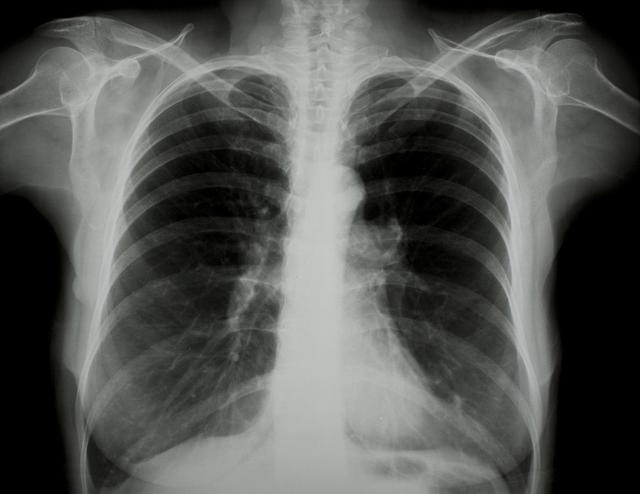

涪陵地區(qū)最新肺炎情況顯示,疫情形勢嚴峻。目前,當(dāng)?shù)卣歪t(yī)療部門正在積極應(yīng)對,采取一系列措施控制疫情傳播。具體感染人數(shù)、癥狀表現(xiàn)、疫苗接種情況等仍在持續(xù)更新中。請廣大市民密切關(guān)注官方發(fā)布的信息,做好個人防護,共同抗擊疫情。涪陵地區(qū)肺炎疫情嚴峻,政府積極應(yīng)對,請市民關(guān)注官方信息,加強個人防護。

據(jù)最新官方數(shù)據(jù)顯示,涪陵地區(qū)肺炎病例數(shù)量令人擔(dān)憂,截至目前,涪陵地區(qū)累計確診肺炎病例XX例,疑似病例XX例,請大家務(wù)必提高警惕,不可掉以輕心。